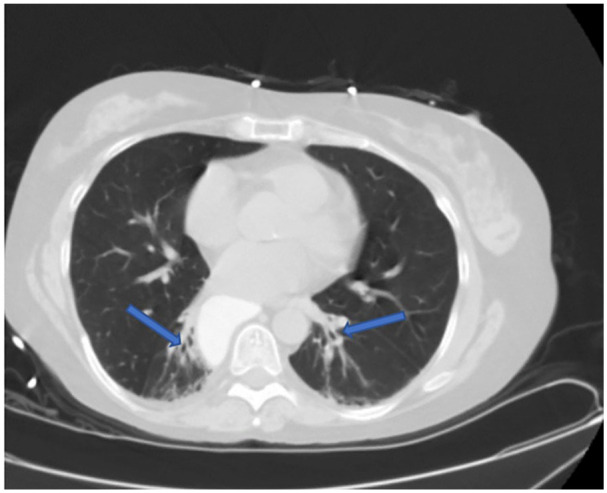

Scleroderma renal crisis is a rare, life-threatening complication of systemic sclerosis. It is characterized by pronounced hypertension, acute kidney injury, and thrombotic microangiopathy. Although its prevalence has decreased over the last decade, and death rates have declined since the introduction of treatment with Angiotensin converting enzyme (ACE)-inhibitors, it remains a challenge due to lack of prevention and rapid progression despite intervention in those who develop renal crisis. We present a 46-year-old female with history of rheumatoid arthritis and scleroderma who presented to the Emergency Department (ED) with complaints of a severe headache associated with nausea and vomiting that started earlier in the day. Patient presented with a blood pressure of 180/103 that did not improve with use of anti-hypertensive medications. Labs were remarkable for anemia and decreased renal function. A CT of the abdomen and pelvis without contrast demonstrated distention of distal esophagus with possible underlying esophageal dysmotility due to degree of distention and dependent areas of tractional bronchiectasis in the bilateral lower lobes that can be seen in the setting of early interstitial lung disease. Treatment with an ACE-inhibitor was initiated, with improvement in blood pressure and resolution of headache. This case demonstrates another rare case and illustrates the importance of rapid recognition and treatment.